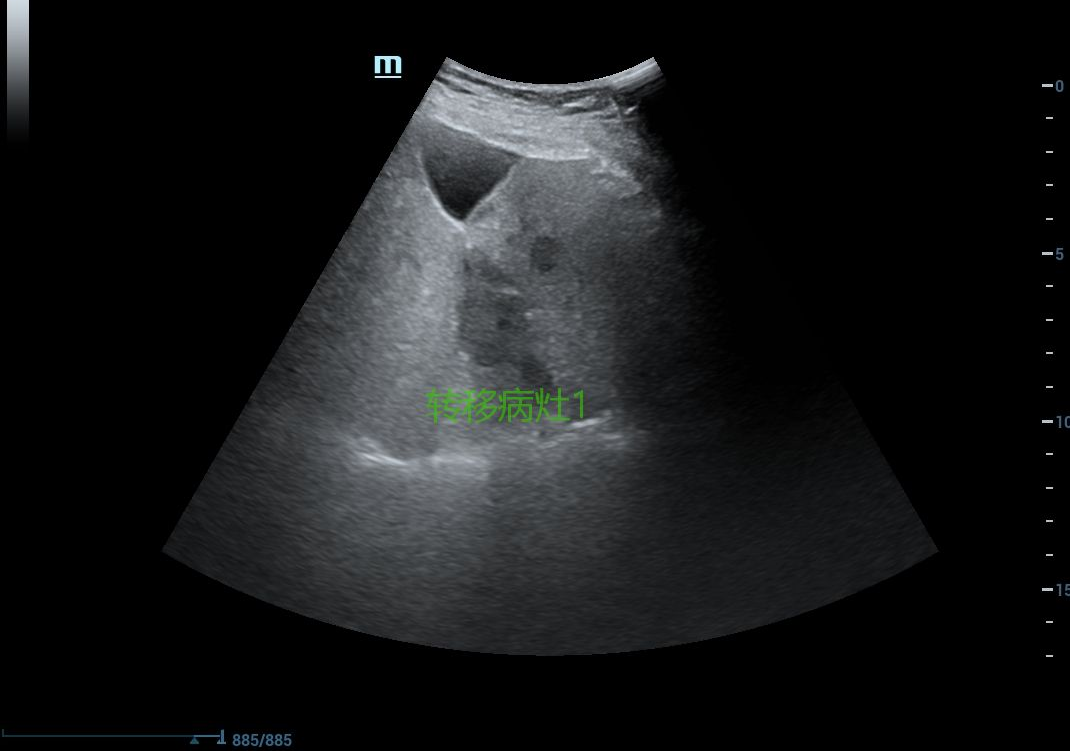

结肠癌肝转移患者多发转移病灶

2.转移性肝癌(如结直肠癌肝转移)。